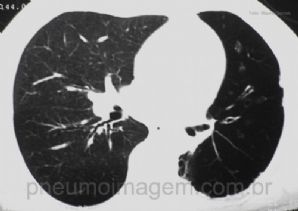

CASO CLÍNICO #1

Paciente do sexo masculino, 56 anos, apresenta dispneia há 10 anos, progressiva, atualmente aos pequenos esforços. Ex-tabagista 20 anos/maço, há 20 anos sem fumar. Hipertenso em uso de amlodipino 5mg/dia e losartana 50mg/dia. Ao exame clínico apresenta-se o...